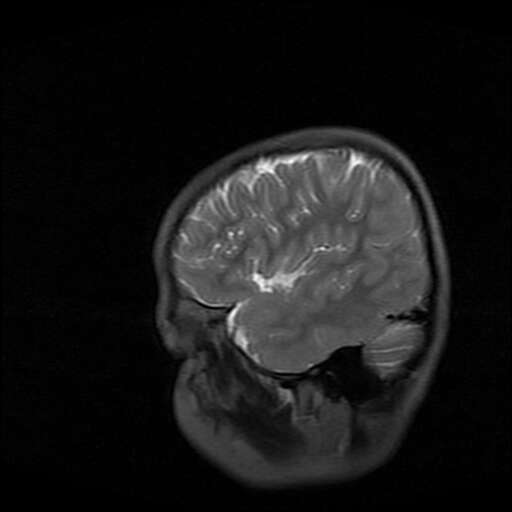

女,7岁,三岁才说话、走路。现智力尚可,走路不稳。临床怀疑大脑发育不全。

考虑 脑白质发育不良

脑折质变薄,双侧侧脑室稍扩张,支持考虑脑折质发育不良

侧脑室周围白质软化症。

考虑胼胝体发育不全,髓鞘形成不良。

支持考虑胼胝体发育不全,髓鞘形成不良。

脑裂畸形伴灰质异位

侧脑室周围白质数量减少,侧脑室不对称性扩大,左侧侧脑室后角呈方形改变,脑沟加深,结合临床考虑脑室周围白质软化症(pvl)。期待结果!

只看出灰质异位

支持脑白质发育不良。